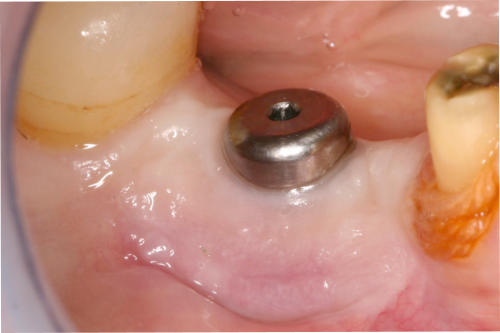

Durch Transplantate kann verlorenes Gewebe wieder aufgebaut werden. Damit wird eine dauerhafte Stabilität der Gewebe und damit auch des Knochens erzielt und eine gute Putzfähigkeit für Zähne oder Implantate erreicht. Beispiele:

Mikrochirurgischer Wundverschluss

Gingivatransplantat fixiert

Zustand 3 Wochen post OP